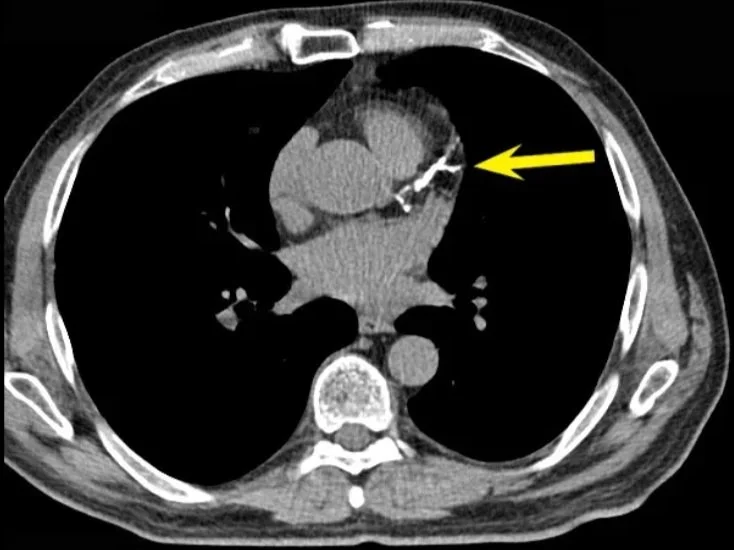

2. CT Angiogram

Think of it as CAC’s more detailed cousin.

Provides high-resolution images of the arteries and blood flow.

Helps identify both soft and hard plaques, offering a deeper look—especially important if there’s a family history of heart disease or unexplained symptoms.